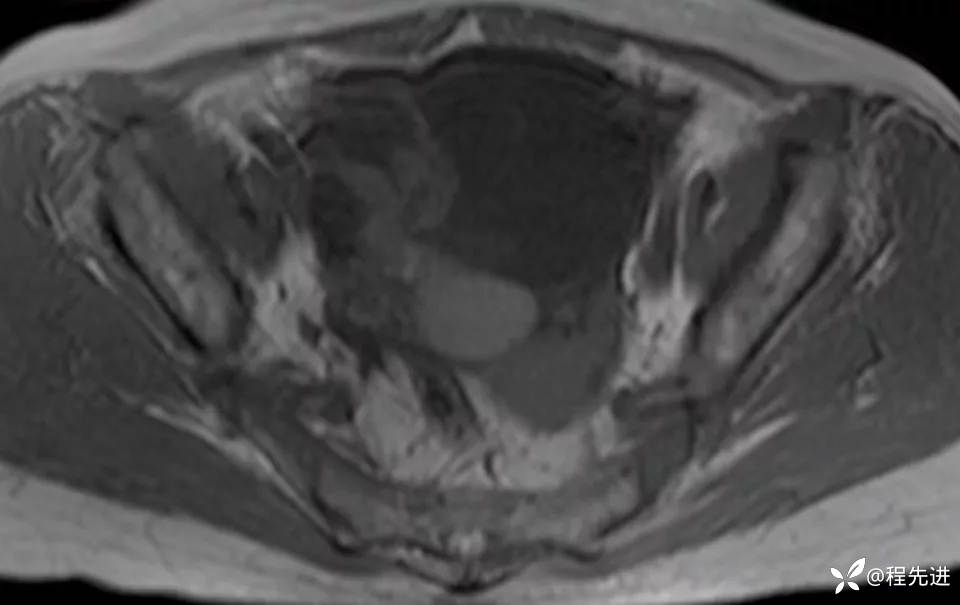

MRI平扫+增强: